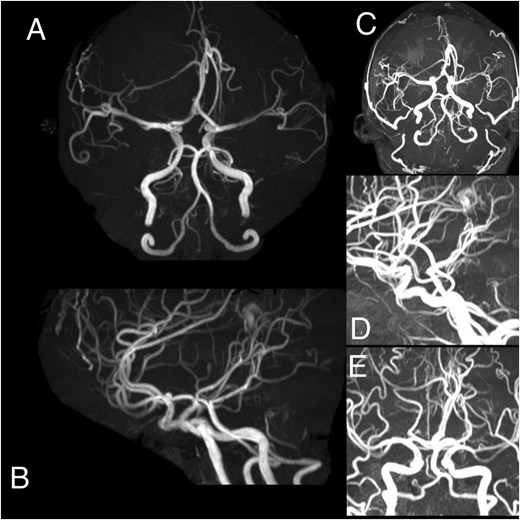

(A–E) Angiography demonstrates a hypervascular space-occupying lesion supplied by branches of the right anterior cerebral artery, right middle meningeal artery, right superficial temporal artery, left anterior cerebral artery, left middle meningeal artery, and left superficial temporal artery.